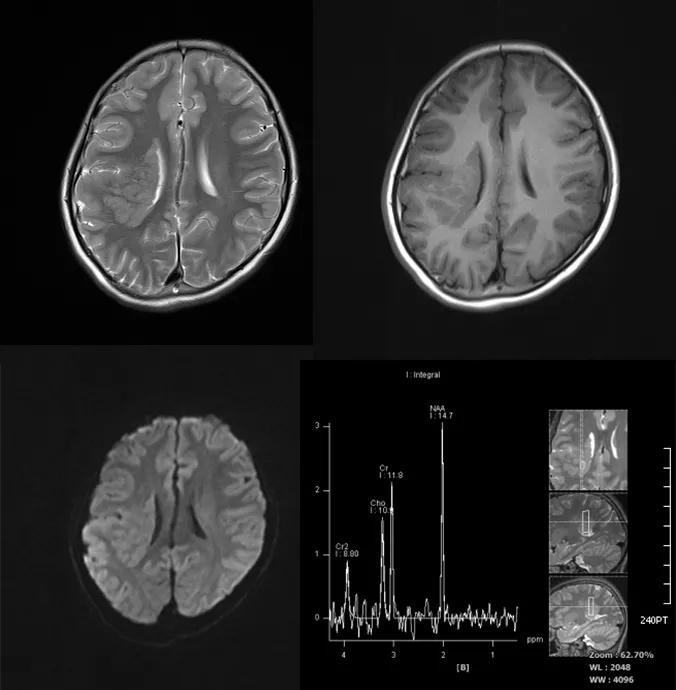

灰质异常

灰质异位(Heterotopias)是一种先天性疾病,是由于胎儿时期神经元或未分化的细胞沿放射状胶质细胞纤维移行过程中受阻,未移行或停留在脑白质区形成异位的灰质结节

较小的灰质异位可无症状,其常见症状主要有癫痫发作、精神呆滞及脑发育异常。癫痫患者中 5%-10% 由灰质异位引起

主要影像表现为脑白质区见灰质密度或信号,增强扫描示病灶与正常脑皮质的强化一致,一般无占位效应,较大病灶可有占位效应,但其典型的灰质信号,增强无强化可与其它病变鉴别

case 1:女性 ,14 岁,反复癫痫发作。

诊断:右侧脑室旁灰质异位。